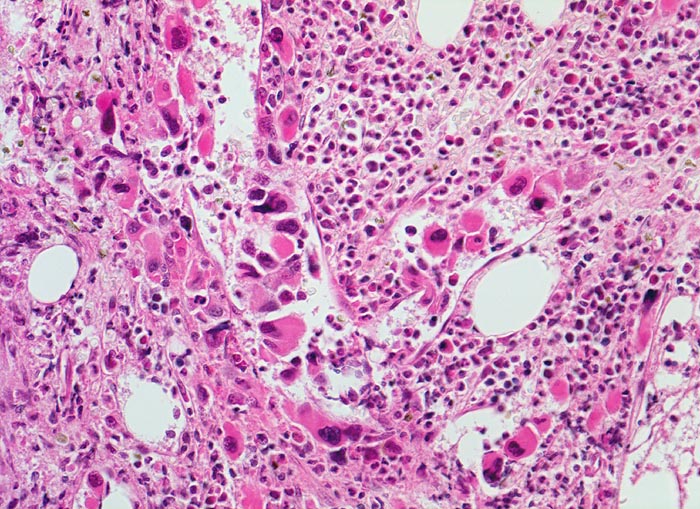

- Osteosklerose: verplumpte und breite Knochenbälkchen.

- Kollagenfibrose.

- Dilatierte Sinusoide mit intrasinusoidaler Blutbildung.

- Vermehrung von atypischen, in Gruppen liegenden Megakaryozyten mit abnorm lobulierten Kernen.

- Nacktkernige (zytoplasmaarme) und vergrösserte Megakaryozyten.

- Hyperplastische ausreifende Myelopoese.

- Hypoplastische Erythropoese.

- Retikulinfaserfibrose des Marks vorhanden aber in der HE Färbung schwierig quantifizierbar.